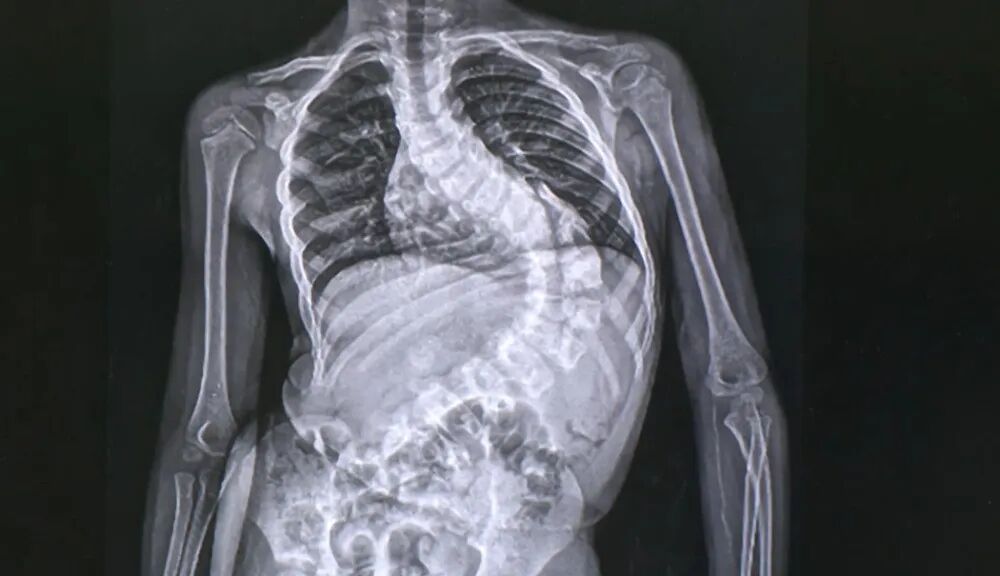

诊断脊柱侧弯的方法很简单,拍摄一个站立的全脊柱正侧位X光片即可。如果有侧弯,X光片可以清楚地显示出来

图片